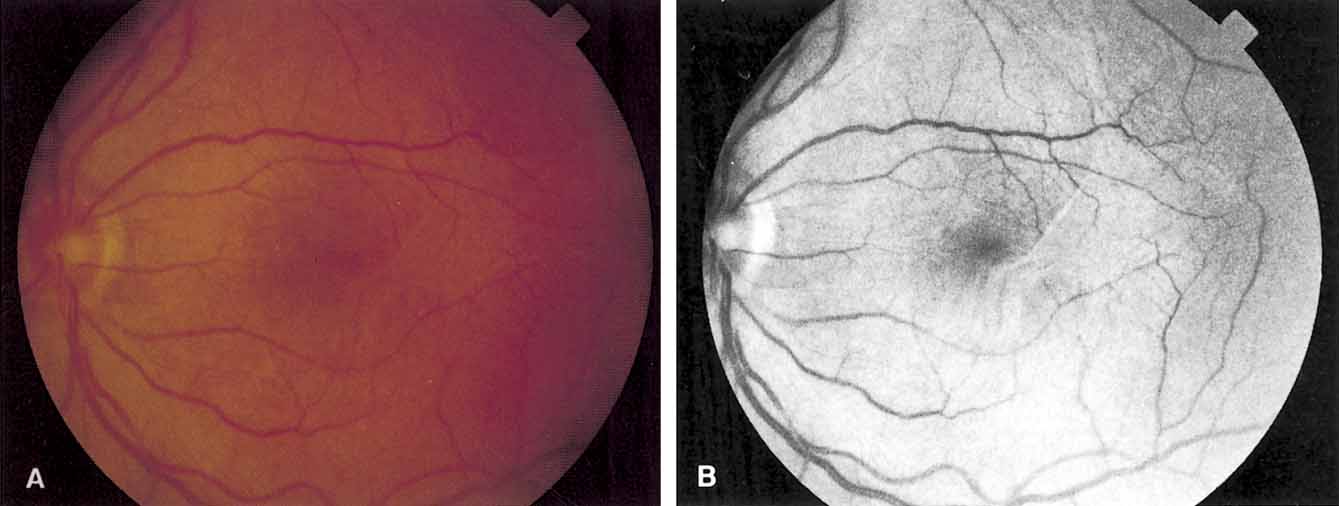

The clinical appearance is variable and may present as only a mild sheen or glint in the macular region that can best be seen with red-free or monochromatic green or blue light (Fig. 5). In more severe cases, there is increased vascular tortuosity and the perimacular vessels are seen to be pulled toward an epicenter, with striae and heterotopia of the macula. The superior and inferior arcuate vessels are also closer together and straighter than in an uninvolved eye. Other findings that may be present include small intraretinal hemorrhages, cystic changes in the macula, macular edema, and cotton-wool spots.110 Pseudoholes or macular cysts have been noted in up to 8% of idiopathic cases (Fig. 6).25,88 Thin membranes may be completely translucent, whereas thicker membranes are frequently opaque or pigmented and generally obscure details of the underlying fundus (Fig. 7).110–112 The thicker and occasionally pigmented membranes are often seen after retinal detachment surgery, severe inflammatory conditions, and trauma. An apparent posterior vitreous separation has been reported by most authors to exceed 75% in cases of idiopathic epiretinal membranes.84–88,93,104,105,113–117 It is sometimes difficult to accurately determine the vitreoretinal relationships preoperatively.

Fig. 6 A. Idiopathic epiretinal membrane with macular pseudohole in a 35-year-old woman. B. Postoperative appearance with disappearance of macular pseudohole and improvement in vision from 20/100 to 20/40. (Margherio RR: Epiretinal macular membranes. In Albert R, Jakobiec EA, eds. Principles and Practice of Ophthalmology, Vol. 2. Philadelphia: WB Saunders, 1993:919–925)

Fig. 7 A. Preoperative appearance of thick epiretinal membrane in 10-year-old boy after trauma. B. Postoperative appearance after removal of epiretinal tissue. Vision improved from counting fingers to 20/100. (Margherio RR: Epiretinal macular membranes. In Albert R, Jakobiec EA, eds. Principles and Practice of Ophthalmology, Vol. 2. Philadelphia: WB Saunders, 1993:919–925)